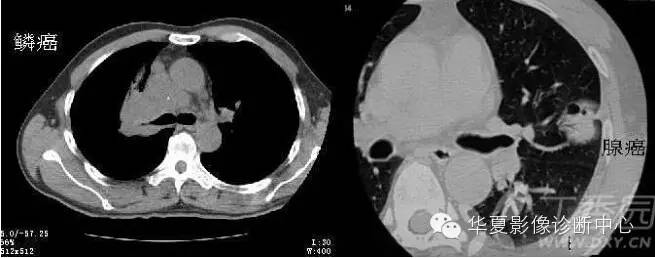

2、横S征(反S征) 医学百科网 | YxBaike.Com

右肺门肿块与右上叶不张相连,形似横写S,为右上叶中央型肺癌特征性表现 医学百科网 | YxBaike.Com